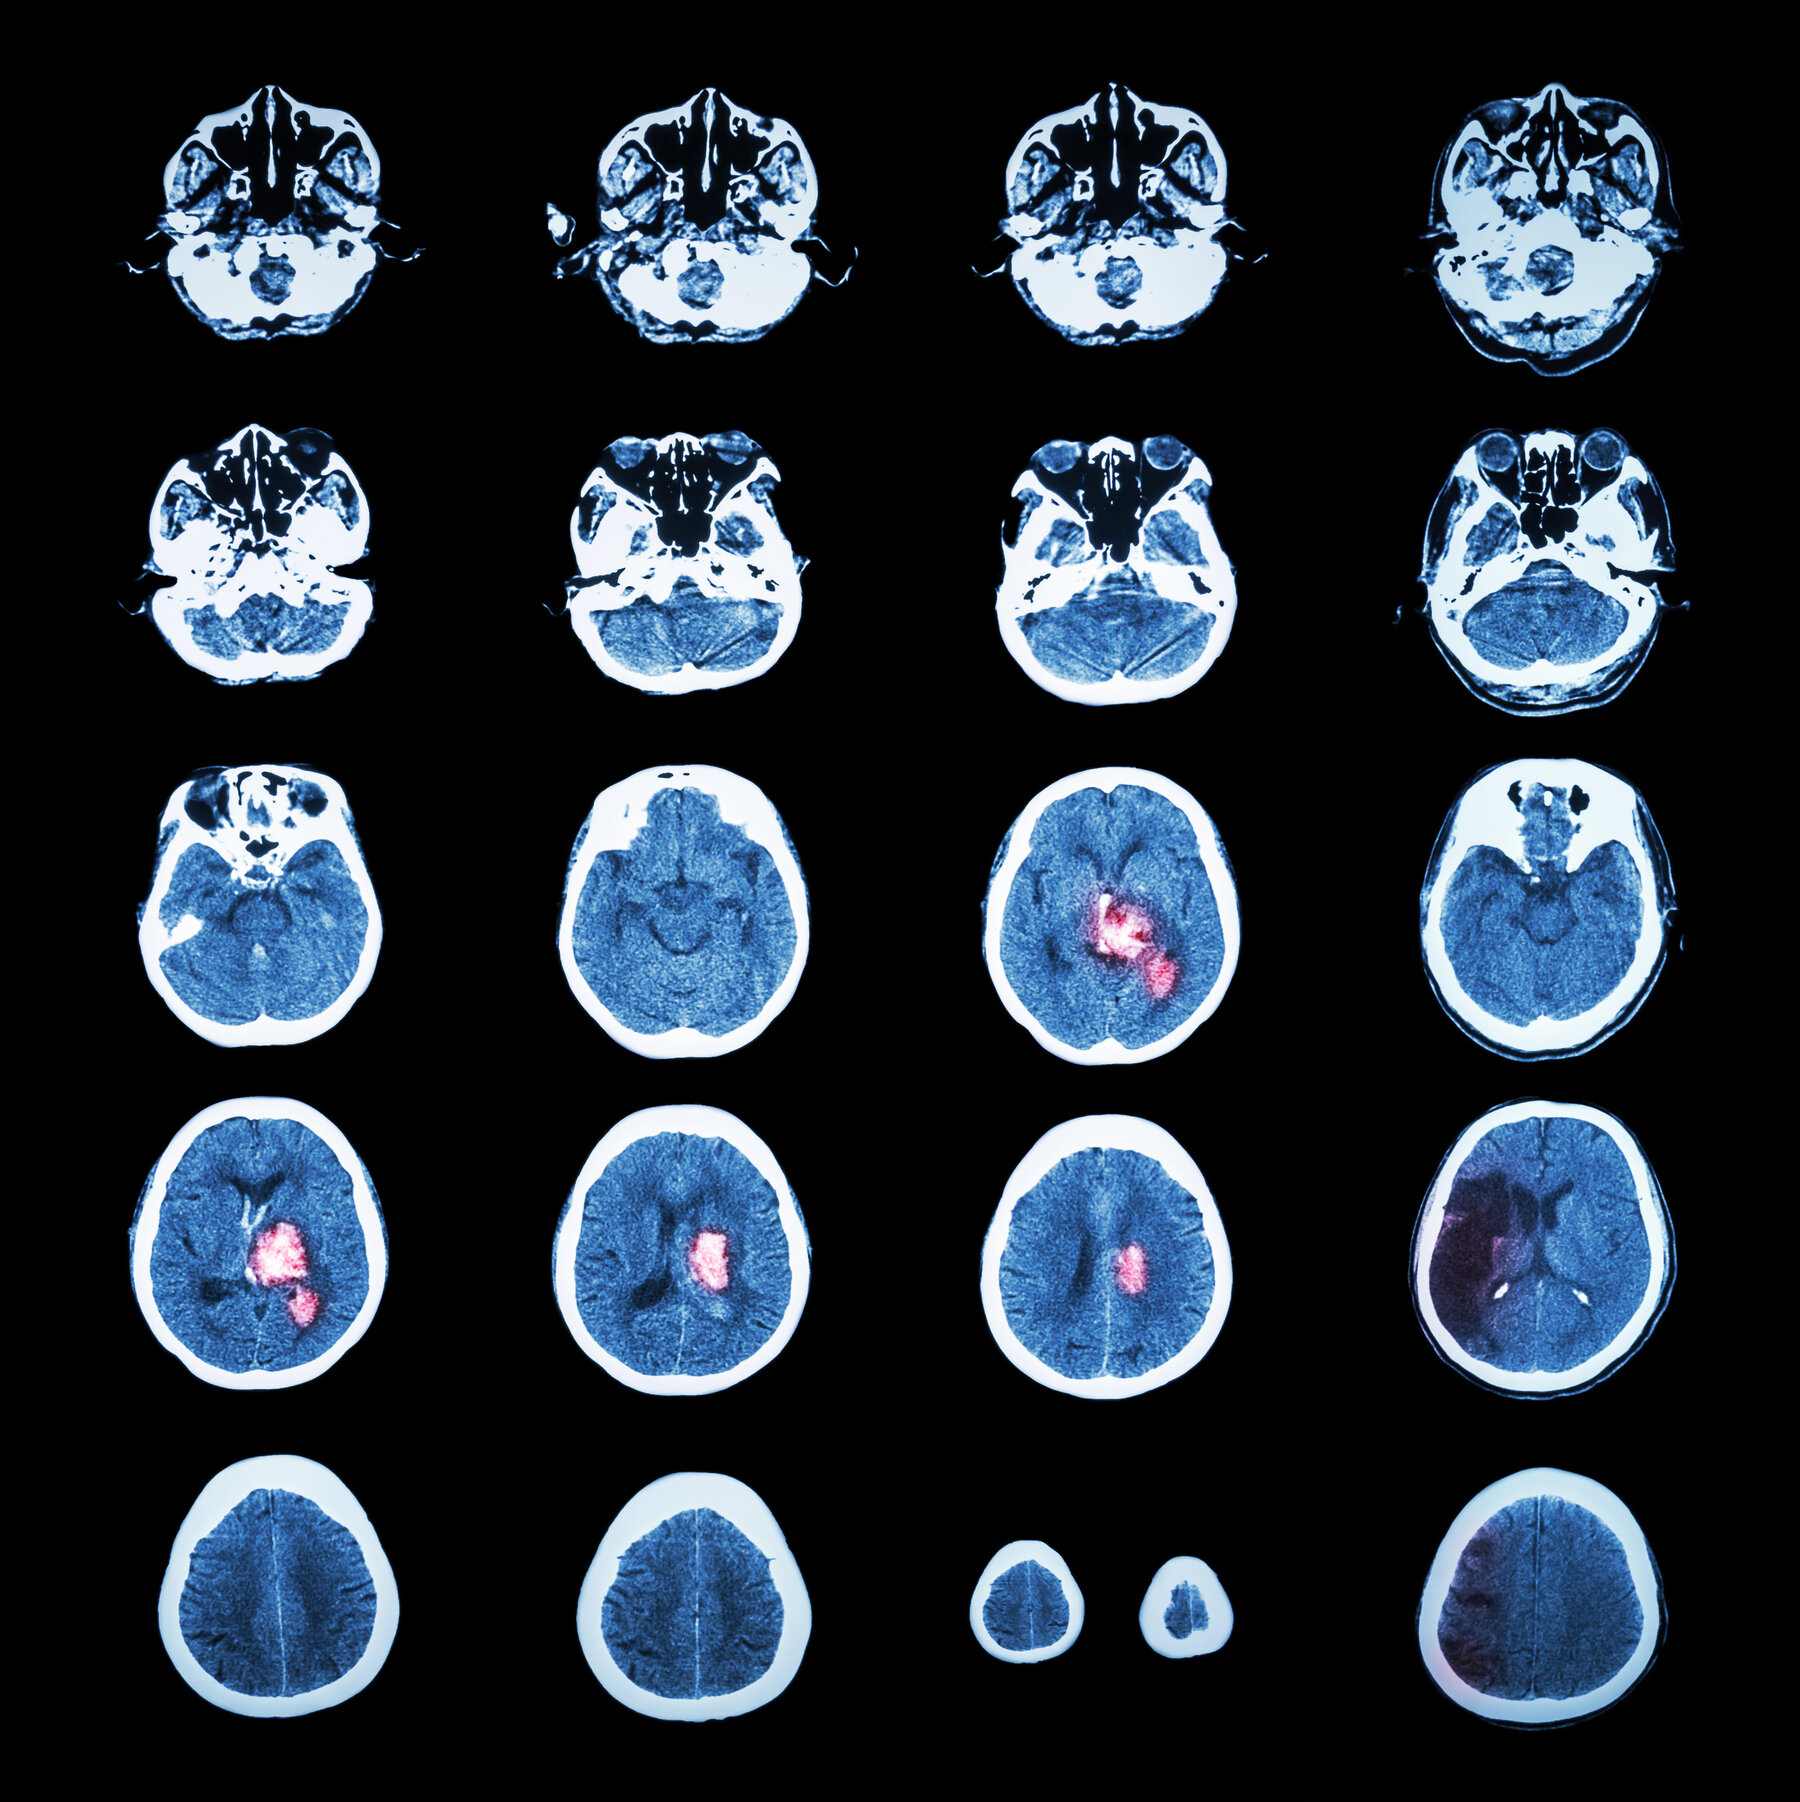

They work for depression and P.T.S.D. Could they also help the brain repair itself after a neurologic catastrophe?

They work for depression and P.T.S.D. Could they also help the brain repair itself after a neurologic catastrophe?